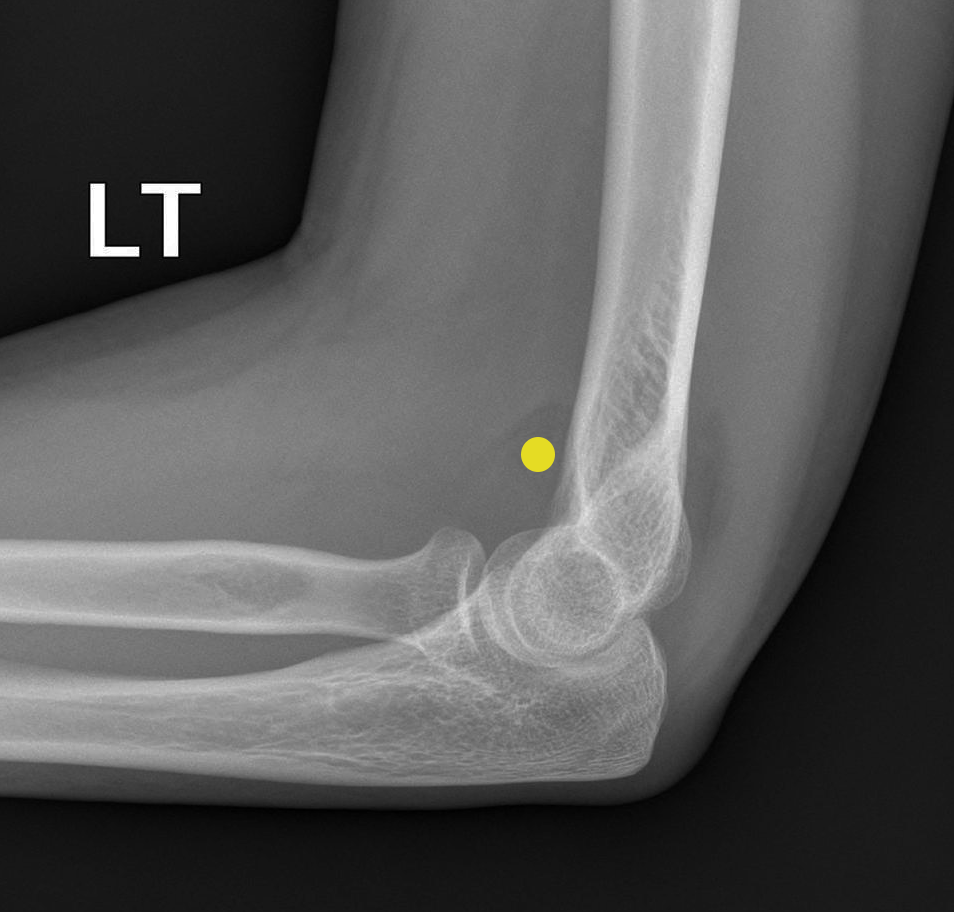

A 30 year old woman fell off a push-bike onto the left arm. A lateral radiograph shows elbow joint effusion, indicated by the 'sail sign' (yellow dot) of the anterior fatpad.

anterior fat pad is visible and raised

posterior fat pad visible

Their visibility is a result of an elbow joint effusion

adult → occult fracture of the radial head

sail sign

anterior fat pad, usually concealed within the coronoid fossa, becomes elevated and takes on a triangular shape

indicates joint effusion

In adults: sign of an occult fracture of the radial head

in children: supracondylar (distal humerus) fracture